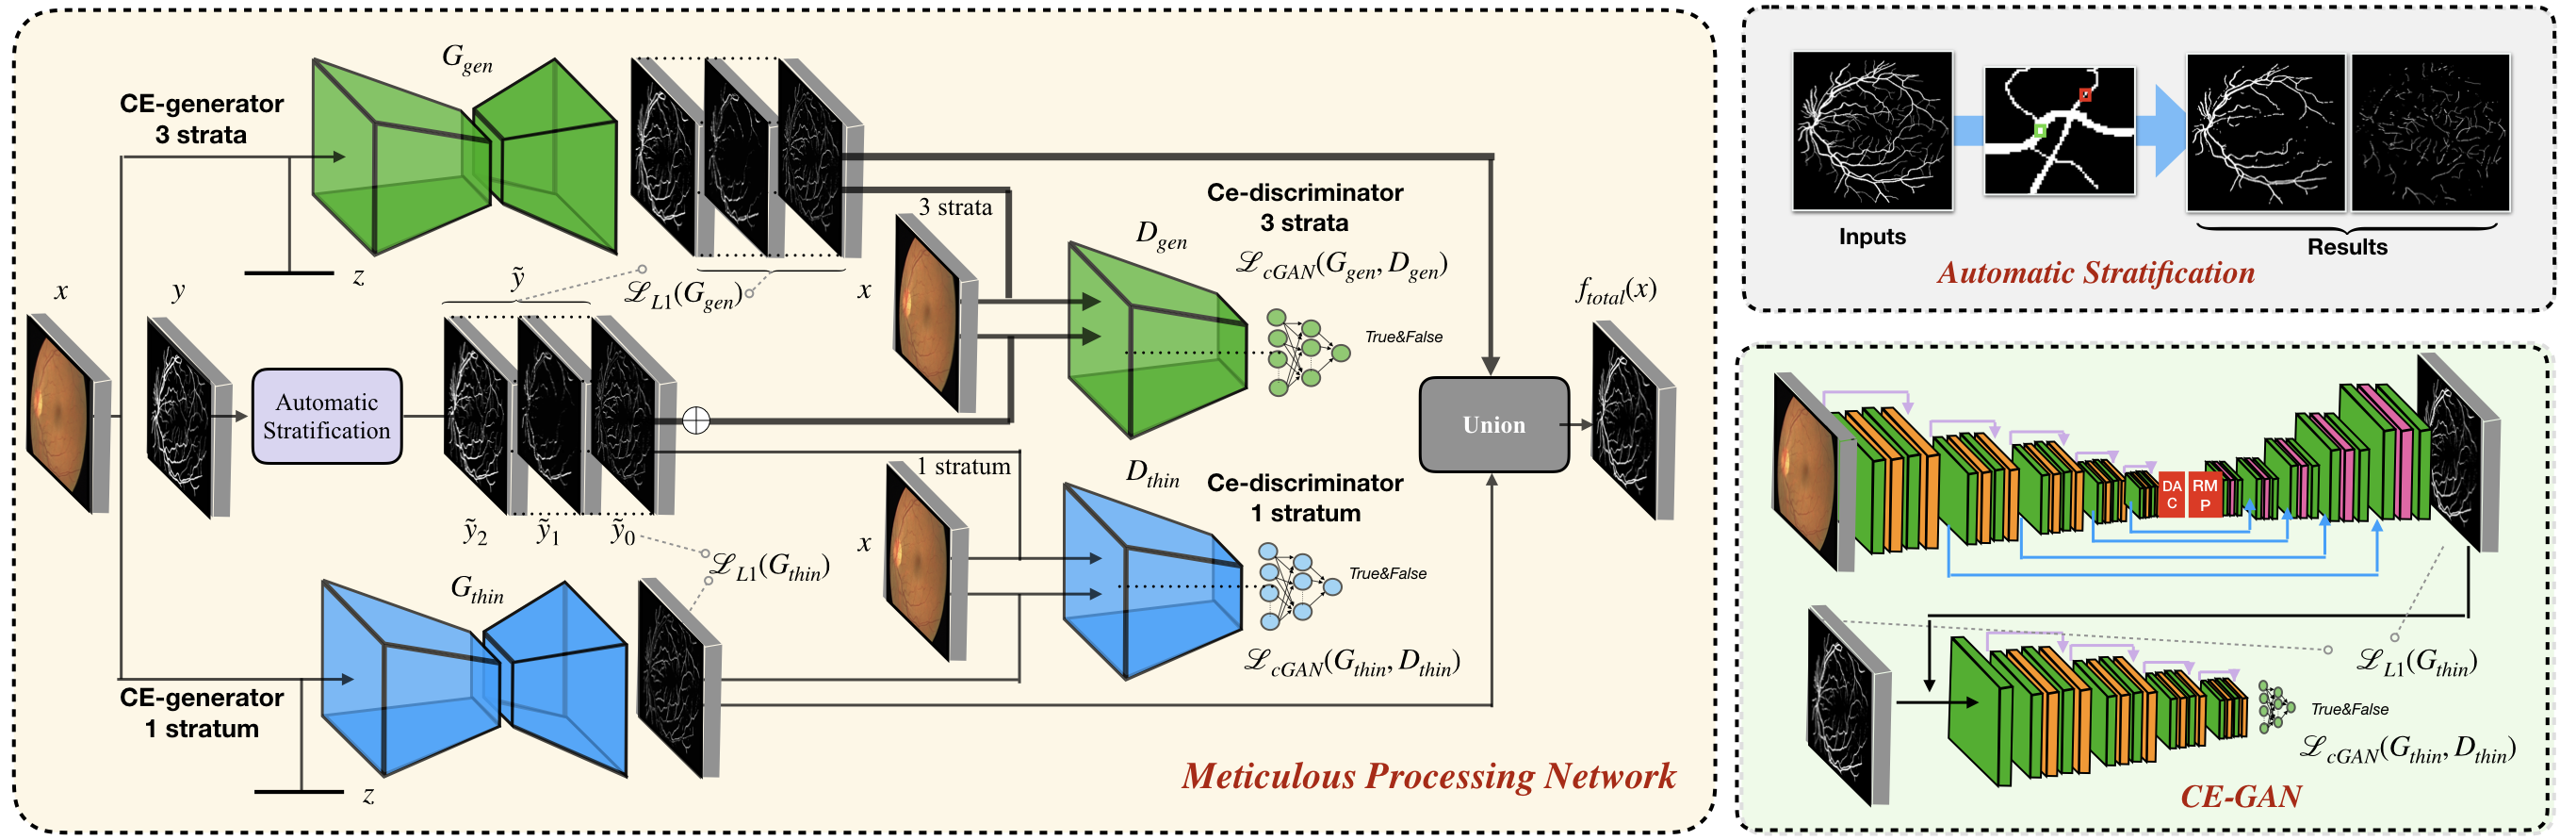

Vessel segmentation in fundus is a key diagnostic capability in ophthalmology, and there are various challenges remained in this essential task. Early approaches indicate that it is often difficult to obtain desirable segmentation performance on thin vessels and boundary areas due to the imbalance of vessel pixels with different thickness levels. In this paper, we propose a novel two-stream Meticulous-Processing Network (MP-Net) for tackling this problem. To pay more attention to the thin vessels and boundary areas, we firstly propose an efficient hierarchical model automatically stratifies the ground-truth masks into different thickness levels. Then a novel two-stream adversarial network is introduced to use the stratification results with a balanced loss function and an integration operation to achieve a better performance, especially in thin vessels and boundary areas detecting. Our model is proved to outperform state-of-the-art methods on DRIVE, STARE, and CHASE_DB1 datasets.

In this paper, we inspect the rationale behind this problem from a perspective of data balancing. The reason that ordinary neural networks did not obtain desirable segmentation performance on thin vessels and boundary areas is that vessel data are suffered from imbalance internal to an assumed identical class (vascular or non-vascular). Vessels with different thickness levels may have different features for identification and localization, making them essentially different classes in a segmentation task. Therefore, balancing across these classes becomes an important work to avoid bias in learning. However, such balancing remains challenging as in most available segmentation datasets, the ground-truth mask is binary, providing no immediate information regarding thickness levels. In view of this challenge, we propose a novel morphological model that automatically segments and classifies (stratifies) ground-truth masks into strata regarding vessel thickness levels using hierarchical opening operations. In order to further increase the segmentation performance, we also propose a two-stream model that learns both general retinal vascular features and those specific to thin vessels and boundary areas by processing both all strata and only the thin vessels (the following ”thin vessels” refer to both thin vessels and boundary areas) stratum. The results from the two streams are united (pixel-wise ORed) to output the final result.

Our contributions mainly lie in 3 aspects. (1) We propose a novel two-stream architecture to synthesize features of different thickness levels. (2) An efficient hierarchical model of opening operations, which automatically stratifies the ground-truth masks to inject thickness levels sensitivity to our model and is jointly utilized with a proposed CE-GAN model whose generator is based on the CE-Net [5] architecture. (3) A balanced loss function and an integration operation to unify and enable weighing on vessel classes of various thickness levels.

2.1 Automatic Stratification

For each original sample , the mask is stratified into componential masks (strata): , each with only the vessel labels of the corresponding thickness levels. The stratification is achieved via opening (erosion then dilation) with thresholding kernels. For the opening operation, we apply thresholds for kernels sizes: , . We define the diameter of the vessel as the discrete Fréchet distance between its two border curves and :

2.2 Two-stream Model

In order to learn vessel features of different specificities, we propose a novel two-stream model for both general features and those especially related to thin vessels. On one stream, learns general features via training against 3 strata. To effectively learn the features of different thickness levels, we propose to concatenate both the two stratified masks (stem and thin) and the original mask (raw) along a third, strata dimension to form of shape for later training. Samples with stratified masks are fed to a general end-to-end U-Net-like segmentation network that outputs a prediction map against each strata. On the other stream, an additional end-to-end network dedicated for segmenting thin vessels outputs only one prediction map against only the stratum of thin vessels labels .

The segmentation problem can also be formulated as an image-to-image translation task from the original image to the ground-truth mask. Specifically, we materialize the two-stream network as adversarial CE-GAN models. Under this context, we train the generative networks from those following loses:

In addition, generators are also trained directly against the ground-truth strata to refine the segmentation results with L1 norm and . Moreover, the adversarial segmentation networks are updated using a min-max algorithm, where the losses of the above two training ends are regularized by a hyper-parameter :

Since both the two networks produce smooth predictions, first we binarize the preliminary outputs with a threshold of 127. Then as the final outputs of our system, positive binarized predictions are united (pixel-wise ORed) with that from each prediction maps.

To justify the performance of our model, we compare the 4 metrics with 8 representative previous works from all 3 open-access datasets. The comparison results presented in Table 1 show that our MP-Net model outperforms the state-of-the-art methods regarding accuracy and in all three datasets, which meter the practical prediction quality and the overall prediction quality independent on thresholding specifications. The advancement is greater in the DRIVE dataset. It’s related to the fact that the DRIVE dataset contains more thin vessels, which is the main target of our model. Specificity is also the highest in DRIVE and CHASE_DB1 while sensitivity is highest in STARE. Particularly, our method outperforms ML-UNet [2] and JL-UNet [4] which adopt a different multi-class approach to also especially tackle the thin-vessels challenge. Figure 2 shows an example of our segmentation maps on DRIVE. As can be seen, most thin vessels and boundary areas have been meticulously picked up.

Our proposed MP-Net can be roughly decomposed into 4 major progressive phases: (1) the backbone Context-Encoder Network (CE-Net) as a standalone generator segmenting non-stratified images, (2) the non-stratified CE-Net in (1) together with a discriminator to form a CE-GAN, (3) CE-GAN with a stratified CE-Net (i.e. with raw, stem, and thin strata) to form one stream of the MP-Net, and (4) The one-stream MP-Net in (3) with another stream of thin-stratum-specific GAN in (2) to form the complete two-stream MP-Net. We perform a whole series of ablation studies on all the datasets to verify the effect of each component via separation. The results in Table 2 validate that the stratification and mingled training mechanism and thin-specific designs are both effective improvements to the baseline system.